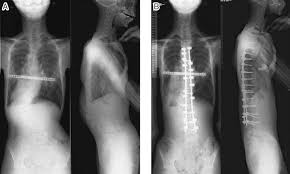

Figure3 A 13 Year Old Male Patient With Syndromic Scoliosis Marfan Download Scientific Diagram